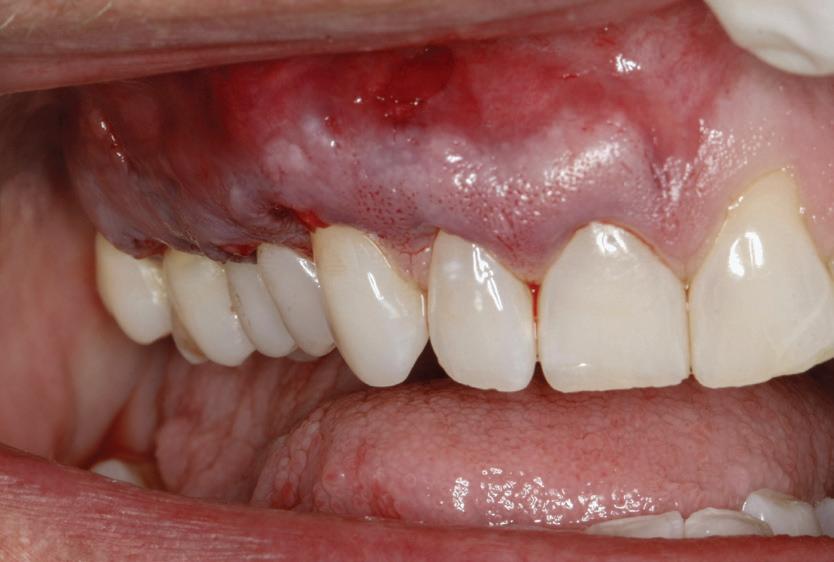

• Similar altor tehnici din stomatologie, procedurile utilizate pentru augmentarea țesuturilor moi ale rădăcinilor denudate au evoluat de-a lungul anilor. Accentul se pune astăzi pe cele minim invazive, parodontologii depunând eforturi pentru o predictibilitate mai mare, cu morbiditate locală scăzută. Regăsiți descrisă tehnica smile (labială sulculară internă modificată) cu tunelizare combinată cu xenogrefă și PRF, care necesită semnificativ mai puține instrumente decât alte proceduri comparabile.

Tehnica SMILE pentru augmentarea gingivală: etape, cazuri clinice